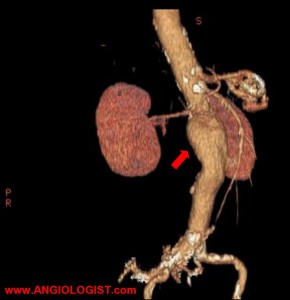

An infra-renal location means they are in the portion between the renal arteries and the iliac bifurcation. When the abdominal aorta diameter exceeds 3 cm it is considered an aneurysm. In the thoracic aorta the cutoff is 4 cm. The reason for the differential cutoff in aortic diameter is that the normal diameter for the thoracic aorta is larger than for the abdominal aorta.

Other imaging studies used are computed tomography with contrast material and when needed CTA (computed tomography angiography) and magnetic resonance angiography (MRA). Having said that, the “gold standard” for aortic aneurysm imaging is still contrast-angiography. Often before a definitive decision is made regarding treatment, a patient will have to undergo formal angiography.